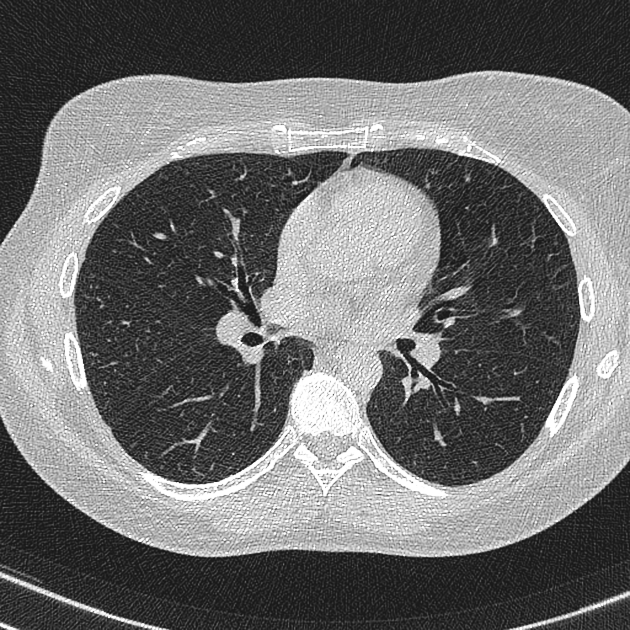

PACIENTE 35 ANOS, SEXO MASCULINO, DISPNÉIA HÁ 4 DIAS.

opacidades em vidro fosco difusas associadas a espessamento de septos interlobulares (crazy paving)

PROTEINOSE ALVEOLAR